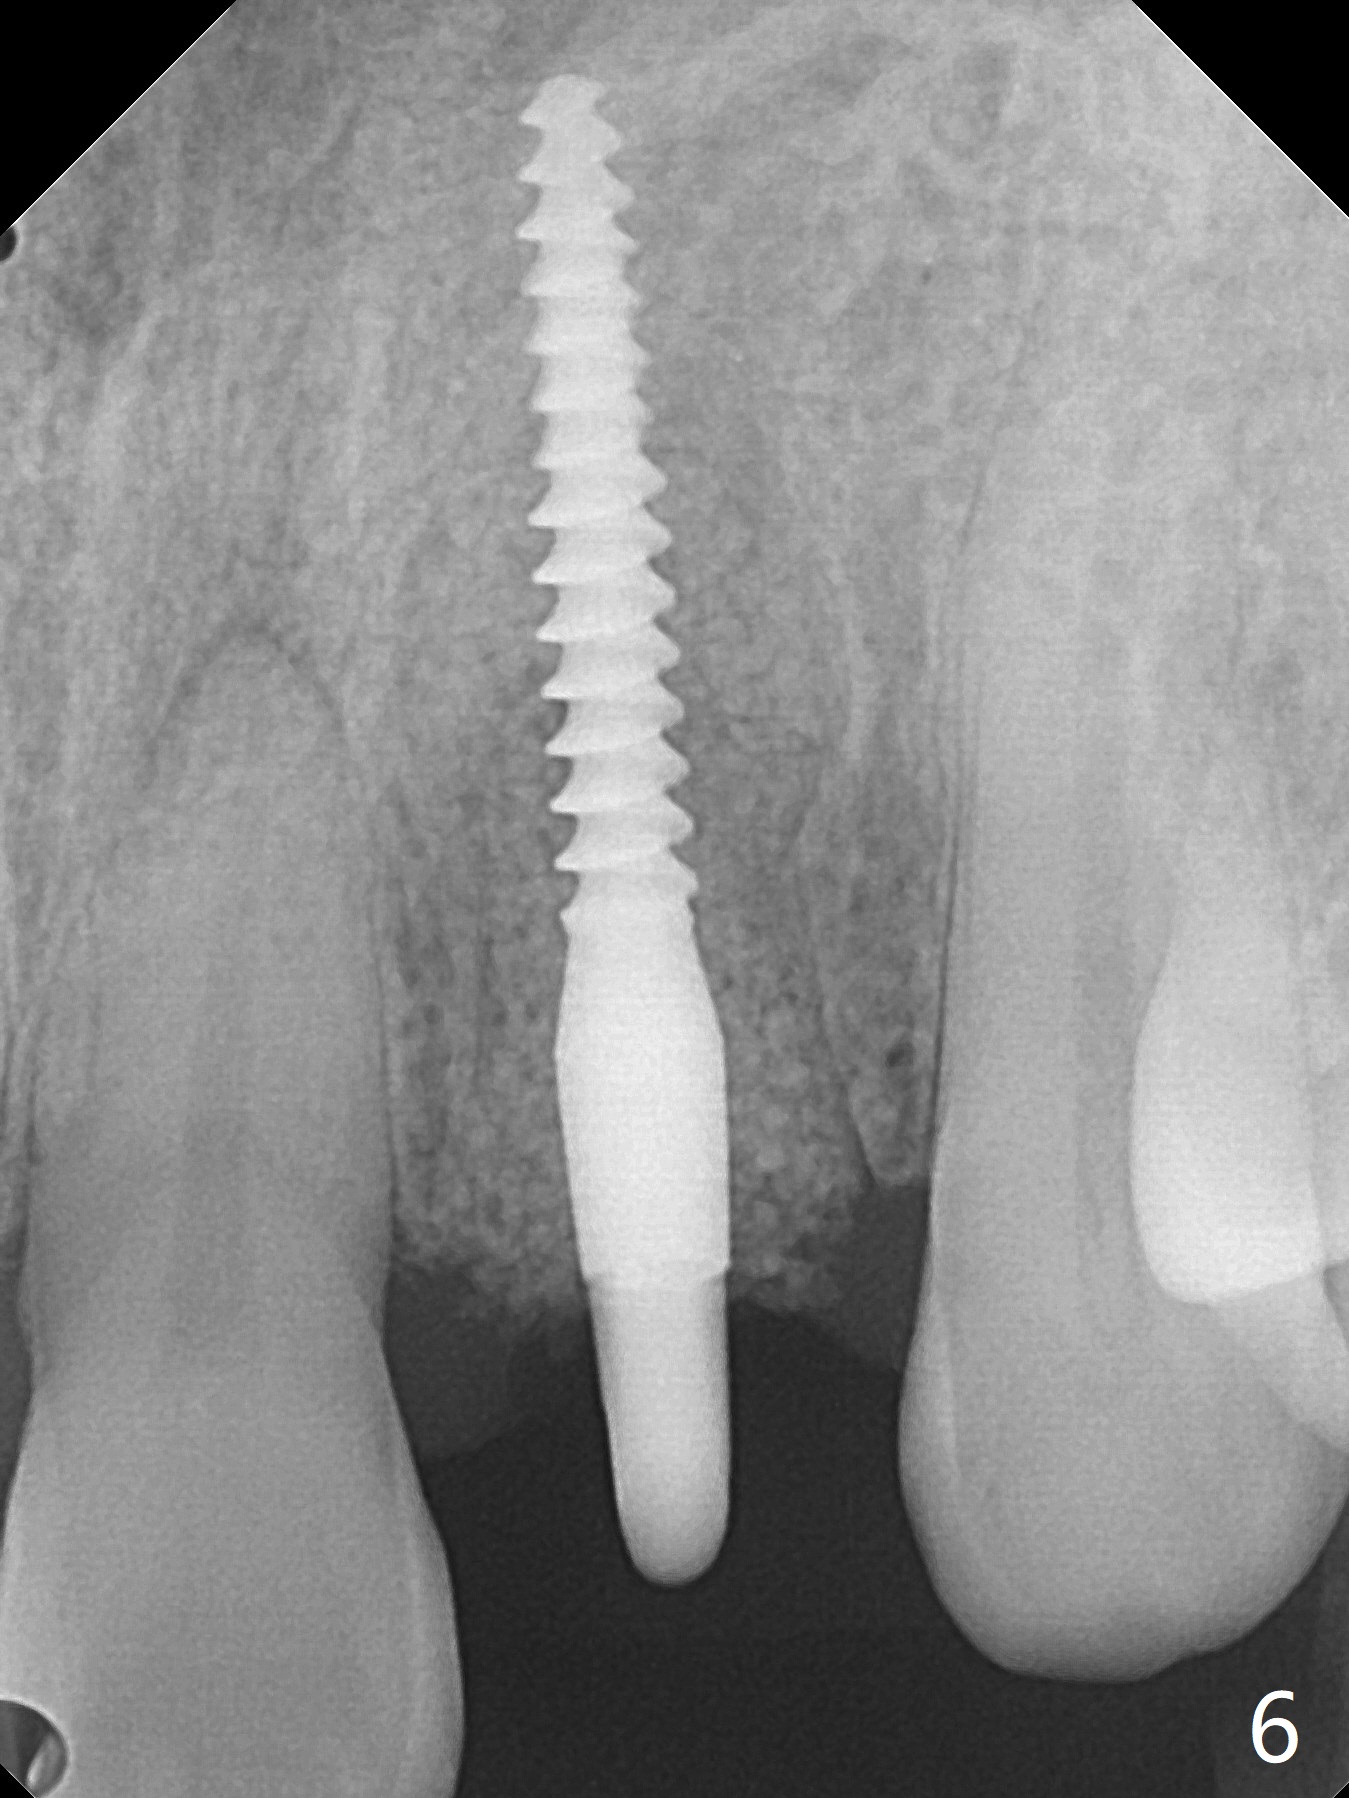

病人回来带来瘘道(图一),不过不会增加难度,病牙去除,它便自动消失。尽管颊侧骨壁完全失去,颊侧牙龈仍丰满(图二),为什么呢?第一,因为粗大牙根存在,第二两旁牙齿,牙槽骨撑着帐篷(侧切牙颊侧牙龈),第三,牙冠。为了防止术后牙龈塌陷,尽量不切开,即刻放置植体(牙根);由于前牙缘故,这次植体不能很大,所以植骨必须过度(over grafting),最后即刻制作临时牙冠,撑住牙龈。这就是所谓每个人进入角色。这个牙根有一种先天性畸形:dens in dent (图三(腭侧观):箭头)。尽管腭侧牙根畸形,腭侧骨壁吸收临床上并不严重,所以钻洞仍偏腭侧。当预定最后钻头还在钻洞时,填入大量粘性骨块(图四:*),细长植体还没有完全卡入鼻底(图五),最后好像可以(图六,七)。植体,骨粉入位(图八),最后临时牙冠出场(图九)。尽管植体小,术后一周临时牙冠仍然可以维持牙龈原有形状(emergency profile,图十:箭头(*:树脂强化牙冠固定))。图十一以不同角度显示瘘道缩小。术后三周取出有些松动的临时牙冠,骨粉虽然还没有被肉芽组织整合,但是显得正常,周围牙龈健康(图十二)。术后4个月牙龈形态正常(图十三),没有触痛;颊侧骨板轻度凹陷(图十四);骨粉仍在原位(图十五)。术后7个月骨粉仍在原位(图十五,十六,但是冠部密度减低(可能骨粉流失,需要牙周或者树脂敷料保护)),没有螺纹暴露。但是牙冠边缘暴露,说明牙龈收缩(图十七,与图十三对比),颊侧骨板仍塌陷(图十八)。插入龈线取得多个目的:修整基台边缘,取模,颊侧牙龈推向颊侧,有利于即将衬里牙冠龈缘进入龈下(图十九)。取模后牙冠边缘(图二十:<)衬里,然后修整,变窄,以便插入龈下,促进颊侧牙龈下降(图二十一,二十二)。术后8个月牙冠粘固前牙龈健康(图二十七,八),牙冠(图二十九)固位后,病人满意(图三十),咬合调整(图三十一),注意腭侧粘固粉流出通道(<)。